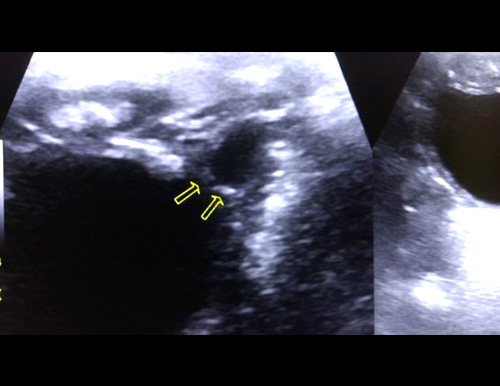

Whole Body Sonography

Ultrasound imaging uses sound waves to produce pictures of the inside of the body. It is used to help diagnose the causes of pain, swelling and infection in the body's internal organs and to examine a baby in pregnant women and the brain and hips in infants.

3D Sonography

Currently, one of the best tools to peer into the body is ultrasound, and more recently, advanced 3D ultrasound. The high-resolution 3D images produced by these types of scans are truly remarkable.